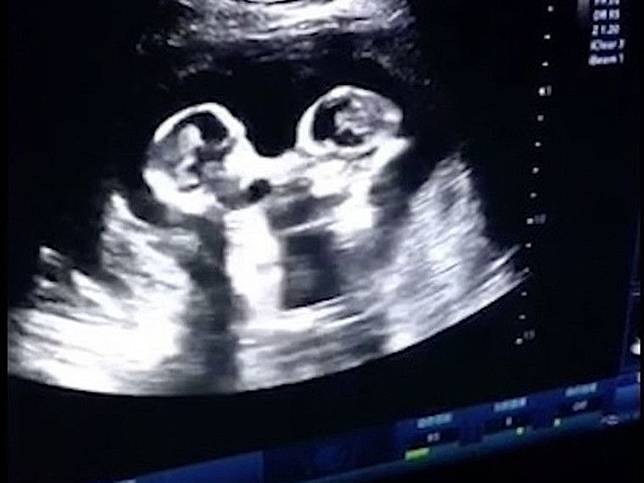

Kenali Cara Membaca Hasil USG Untuk Tahu Kondisi Bayi - Ibupedia Risiko Bayi Lahir dengan Berat Badan Rendah Bisa Dideteksi dengan USG Moms, Begini Caranya Membaca Hasil USG : Okezone Lifestyle 5 Langkah Membaca Hasil USG yang Bisa Bunda Pelajari Terekam USG, Janin Bayi Kembar Ini Saling Adu Jotos dalam Kandungan Ibunya - Semua Halaman - Grid Hot Unik! Tangan Bayi Ini Bentuk Simbol Rock N’ Roll Saat Di-USG Kesalahan Memprediksi Jenis Kelamin Saat Awal Kehamilan - kumparan.com Penjelasan di Balik Bayi Bisa Tersenyum di dalam Kandungan Viral, Rekaman USG Bayi Kembar Bertengkar dalam Rahim - Citizen6 Liputan6.com Tak Usah USG, Ini Cara Sederhana Ketahui Jenis Kelamin Bayi - Tribun Sumsel Orangtua Kaget Bukan Main saat Hasil USG Menunjukkan Bayi Melakukan Simbol Metal - Semua Halaman - Suar Ini Dia Cara Membaca Hasil USG dengan mudah - Mamapapa.id % USG Aman bagi Janin, Asalkan… Waduh, Hasil USG Tidak Bisa Dipercaya 100 Persen - Warta Kota Hiii, Hasil USG 4D Ini Tunjukkan Wajah ‘Bayi’ yang Menyeramkan Penampakan Wajah Misterius Muncul dalam Hasil USG Bayi Ini - Global Liputan6.com Hasil USG Bayi Yang Seram Ini Bisa Kasih Kamu Mimpi Buruk - ANTVKLIK Selain USG, 2 Cara Ini Terbukti Secara Ilmiah Tebak Kelamin Bayi - Berita Riau Terkini TULISAN 11. DETEKSI KELAINAN JANIN DENGAN USG – Dr. Cucuk Santoso Sp.OG Benarkah USG Membahayakan Kondisi Janin di Dalam Kandungan? | Indozone.id Cara Membaca Hasil USG yang Benar, Wajib Tahu! Gambaran Hasil Usg Kehamilan 5 Minggu Yang Perlu Diperhatikan - Hamil.co.id Viral Foto Hasil USG Perlihatkan Janin Kembar Sedang Berkelahi - Citizen6 Liputan6.com Pamer Foto USG, Bayi Nina Zatulini Sudah Mancung di Kandungan Bikin Ngeri ! ini Gambar-Gambar Hasil Ultrasonografi (USG) Terseram - Semua Halaman - Nakita Ini Dia Perbedaan USG 2D, 3D, 4D, dan 5D yang Ibu Hamil Perlu Tahu | BukaReview Manfaat USG untuk Ibu Hamil dan Janin - Ibupedia Pentingkah USG 4 Dimensi? - Mommies Daily Lihat Foto-foto Hasil USG Ini Bikin Merinding, Wajah Bayinya Menyeramkan! - Tribun Lampung Di Indonesia Juga Bisa, Sekarang Ibu Tunanetra Bisa Melihat Bayi dalam Kandungannya - Kompasiana.com Prosedur USG NT Bisa Deteksi Kelainan Janin Lebih Awal | Parenting.Dream.co.id Dokter Jelaskan Hasil USG yang Tampilkan Sosok Bayi Iblis | Republika Online USG BAYI PEREMPUAN DALAM KANDUNGAN USIA 6 BULAN - YouTube Ini Rata-Rata Berat Janin 5 Bulan - Alodokter Viral Video USG Bayi Kembar Berantem Dalam Perut Ini Bikin Gemas - Hot Liputan6.com Viral Foto USG Bayi Disebut Mirip Setan, Sang Ibu Tetap Mencintainya Berapa Kali USG Saat Hamil Harus Dilakukan? Bumil Wajib Tahu, Inilah Penyebab Bayi Sungsang dan Cara Mengatasinya Perkembangan Janin Umur 15W dalam Kandungan - Armita Consultant Gambaran USG janin perempuan usia kehamilan 29 minggu 3 hari - YouTube USG 4D Deteksi Janin Dalam Rahim - Rumah Sakit Permata Cara Membaca Hasil Foto USG Kehamilan - Cara Mengetahui Jenis Kelamin Janin Hasil USG Kehamilan 24 Minggu : “Istriku Hamil Mobil Sport!” | theAsianparent Indonesia Apakah USG Pengaruhi Perkembangan Bayi dalam Kandungan? – Islampos Ibu Panik Karena Corona, Hasil USG Janin Acungkan Dua Jari Ini Bikin Heran | merdeka.com USG foto hasil usg bayi perempuan di bali | wordsof.sandybali.com Story of My Journey: USG Kehamilan 19 Minggu 10 Foto USG bayi ini bikin merinding, mirip karakter film horor Tak Pernah Tes USG, Bayi Ini Meninggal karena Kepala Terjepit saat Lahir Usg bayi tersenyum - IbuHamil.com USG [6] : 34 Minggu 2 Hari – Jejak-jejak yang Terserak Janin Terlihat Lebih Jelas dengan MRI Dibanding USG - Health Liputan6.com Ini Dia Perbedaan USG 2D, 3D, 4D, dan 5D yang Ibu Hamil Perlu Tahu | BukaReview Cute, Bayi Dalam Kandungan Ini Acungkan Jempol Saat USG usg janin bayi 3 bulan ( 14 minggu )… Sujud kepada Allah - YouTube Hasil USG Menunjukkan Janin sedang Meniup Gelembung. Saat Sang Ibu Mengetahui Fakta itu, Dia Merasa Hancur. Lalu Bagaimana Nasib Janin itu? - Erabaru 3 Cara Membaca Hasil USG yang Benar, Biar Nggak Salah Kaprah | merdeka.com JANIN BELUM TERLIHAT SAAT USG? JANGAN KHAWATIR, MOMS! - susistory USG - Bayi Tertangkap Sedang Tepuk Tangan di Layar USG | theAsianparent Indonesia USG 34-37 MINGGU UNTUK TAU BERAT LAHIR… - dr Yudhistya SpOG | Facebook Kapan Usia Hamil Terbaik Melakukan USG? – acehimage.com Potret Malaikat Pelindung di Hasil USG - WinNetNews.com Video USG Kandungan - Lihat Seksama Apa yang Dilakukan Janin Ini di Dalam Perut - Halaman all - TribunStyle.com Cara Menghitung Berat Badan Janin Dari Hasil USG · Terbaru 2019 Ruang Media Foto USG Tampilkan Siluet Iblis Dampingi Janin : Okezone News Pahami Cara untuk Membaca Hasil USG - Tirto.ID Jenis Kelamin Bayi Beda dengan Saat USG, Ini Penjelasan Dokter Ternyata Cukup 3 Kali Melakukan USG Selama Kehamilan, Ini Penjelasannya, Moms! usg kepala bayi – Let The World Surprise You Viral Video Hasil USG Janin Bayi Kembar Seperti Sedang ‘Adu Jotos’ PERKEMBANGAN JANIN 4 MINGGU - 15 MINGGU MELALUI USG 2D / FETAL DEVELOPMENT 4 WEEKS UNTIL 15 WEEKS - YouTube Bisakah Hasil USG Salah Mendeteksi Jumlah Janin? Prosedur USG NT Bisa Deteksi Kelainan Janin Lebih Awal | Parenting.Dream.co.id USG 3D dan USG 4D, Apa Bedanya? Mana yang Lebih Baik? Janin Usia 10 Minggu, Ini Perkembangan yang Terjadi Pamer Hasil USG, Aura Kasih Bahagia Hamil Anak Perempuan Heboh Foto Dan Video USG Bayi Kembar Adu Jotos Dalam Perut – BERBAGI SEMANGAT USG 4 Dimensi Kehamilan Halaman 1 - Kompasiana.com Viral Video USG Bayi Kembar Seperti Berkelahi di Dalam Perut Ibunya - kumparan.com Kapan Kelamin Janin Bisa Di-USG? – . Bikin Ngeri ! ini Gambar-Gambar Hasil Ultrasonografi (USG) Terseram - Semua Halaman - Nakita Diary Kehamilan: USG 4D Murah Meriah – ranselriri Sering USG, Bahayakah Untuk Janin? Ukuran Kantong Janin 6 Minggu Yang Normal Dan Tidak Bermasalah - Hamil.co.id Apakah Pemeriksaan USG Berbahaya Bagi Bayi? - Dokter Indonesia Sains Buktikan Kebenaran Al-Quran Tentang Tiga Fase Bayi Dalam Kandungan | Percikan Iman Online Narsis sejak dalam Kandungan, Janin Bayi Ini Ketahuan Lagi Pose Peace saat USG | Diadona.id Masih di Dalam Kandungan, Dua Bayi Kembar Ini Saling Pukul | Keepo.me | LINE TODAY Amankah USG Bagi Janin? - DokterSehat Hamil 2 Bulan: Dari Embrio Menjadi Janin - Alodokter Ketahui Jenis Kelamin Bayi dengan Jelas Melalui USG 4D Ini Cara Deteksi Bibir Sumbing Bayi Sejak di Kandungan. Bisakah Dicegah? SERAM, FOTO-FOTO USG INI MENANGKAP SOSOK ‘BAYI HANTU’ - KapanLagi.com Langka! Hasil USG Perlihatkan Bayi Ini Tunjukkan Jari Gaya Metal USG foto hasil usg bayi perempuan di bali3 | wordsof.sandybali.com Lagi Tren Nih, Posting Hasil USG untuk Tahu Jenis Kelamin Janin Adi W Gunawan - (Kisah seorang ibu yang mampu… | Facebook Berikut Prediksi Calon Kelamin Bayi Tanpa USG | Destinasi Bandung pemeriksaan usg - Seberapa akurat pemeriksaan USG selama kehamilan? | theAsianparent Indonesia Hasil USG 2D, 3 Dimensi dan 4 Dimensi Perkembangan Janin Bayiku (24 Minggu 2 Hari) #Naya 1 - Danytrikusuma